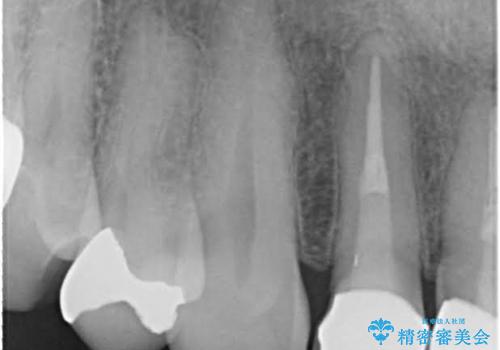

金属だらけの奥歯 根管治療のやり直しとセラミック化

- 神経のある歯を先にセラミック修復し、その後根管治療のやり直しを行う

神経の無い歯のクラウン(かぶせ物)は、根管治療を顕微鏡下でしっかりとやり直し、その後に土台の築造とかぶせ物の製作を行うことで今後問題が生じる可能性を可及的に低くできます。

- 根管治療により痛みや腫れがひかない事や、術後に痛みや腫れが生じる事、治療によるファイル破折やパーフォレーションなどの偶発症、術後の歯根破折を生じる可能性もあります